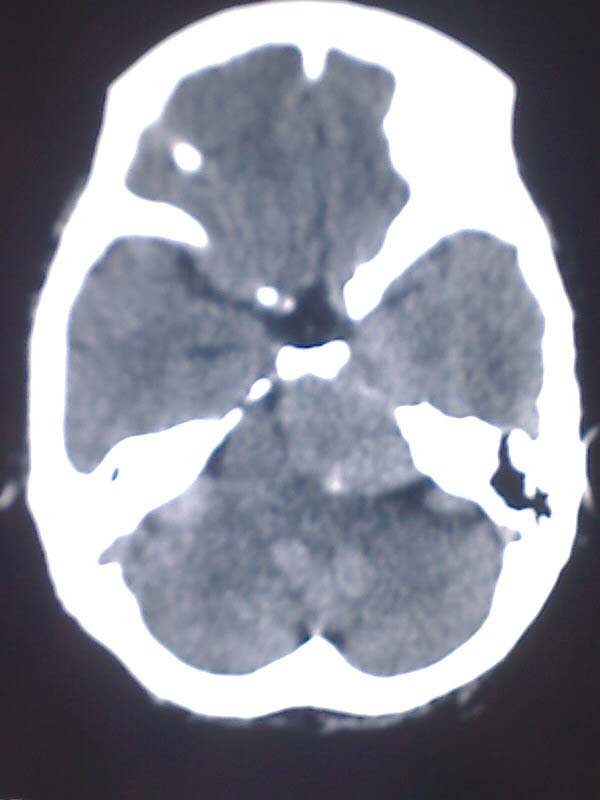

女性,56岁,查体所见,请会诊

平扫为较高密度,增强后病灶明显强化,边界清楚水肿不明显.考虑脑膜瘤.

左岩骨尖区脑膜瘤

从病变位置和强化表现看倾向脑膜瘤,但其跨越中后颅窝,也要结合临床,不能忽略三叉神经瘤,不过后者囊变较多。此病例的不足是无骨窗对照,脑膜瘤比较容易出现临近骨骼的异常。

左岩骨尖区占位病变,平扫呈高密度,病变跨中后颅窝生长,岩骨可见骨质吸收,周围未见明显水肿,增强扫描病灶明显强化。考虑左岩骨尖区脑膜瘤。

此片最大的缺憾是没骨窗,钙化及颅骨的改变不好看